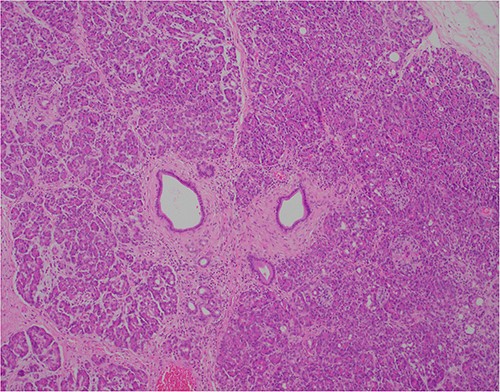

At outpatient phone clinic review 2 months post-surgery, the patient had recovered well, and his pre-operative symptoms of nausea, vomiting and pain had completely resolved. The histopathology of the gallbladder found chronic cholecystitis with cholelithiasis, in addition to a 6 mm focus of pancreatic heterotopia in the gallbladder wall. This heterotopic tissue contained acini, ducts and islet cells, classifying it as Type I pancreatic heterotopia (Figs 1–3).

×2 objective lens; low-magnification photograph showing an area of pancreatic heterotopia.